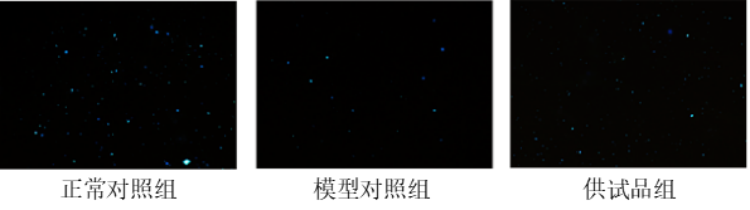

图1. 斑马鱼精子数量表型图

(蓝色颗粒为精子)

从实验结果可以看到。模型对照组的精子数量较正常对照组明显减少,供试品组相对模型对照组精子数量明显增多。